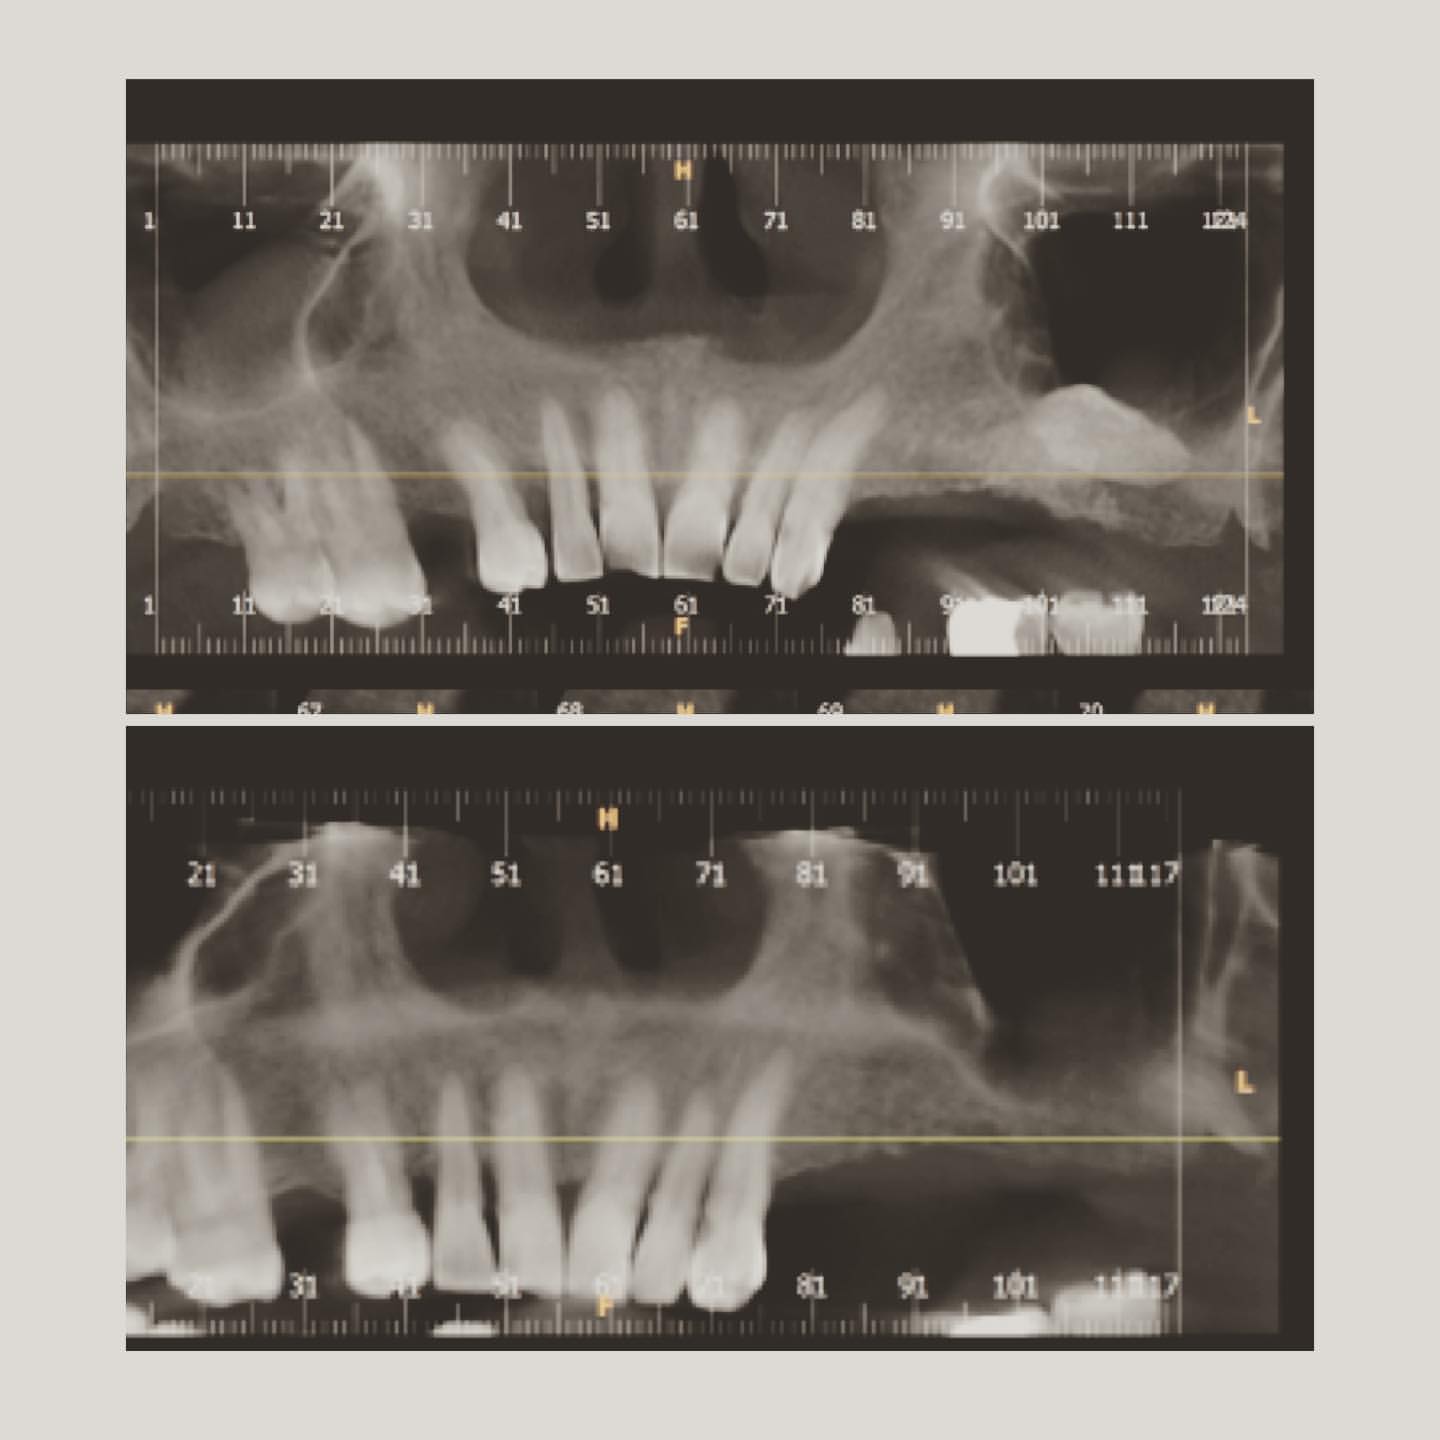

İmplant rentgenləri

Sinus lifting